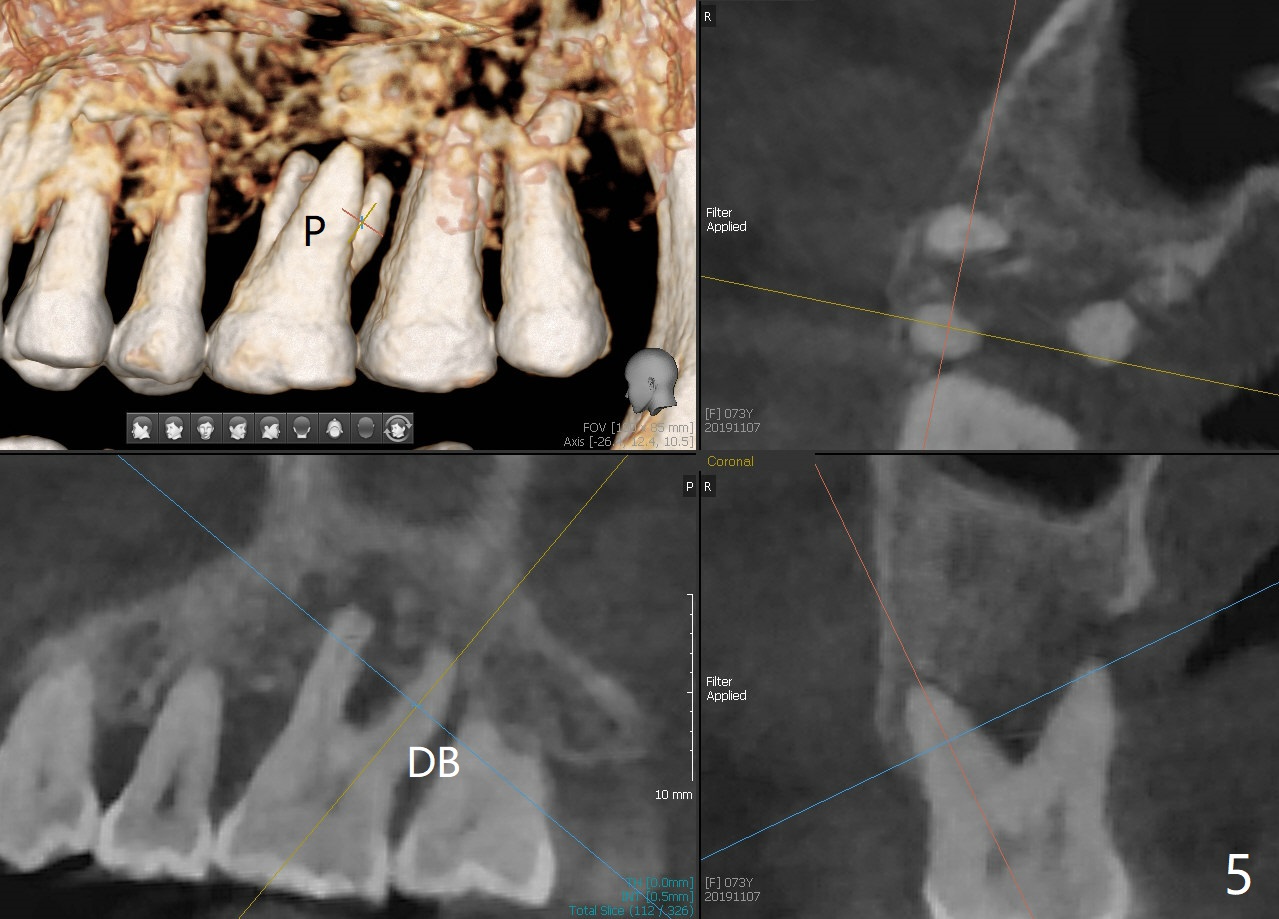

A 73-year-old woman with controlled diabetes has cold and hot sensitivity of the tooth #3. Although the bone loss is striking (Fig.1), mobility is I with the deepest pocket DL ~6 mm. Endo ice induces pain. Extraction and guided immediate implant appears to be the best option (Fig.2 (5x7mm FC)). Note the bone height (2.9 mm) and the thick sinus membrane (M, Fig.2') . B: buccal. Bony defect will be filled with sticky bone and held in place with Cytoplast, while PRF for sinus lift. Because she is afraid of implant, RCT, followed by SRP and possibly periodontal surgery, seems to be viable because of the straight, not-so-narrow canals (Fig.3-5). Due to time constraint, immediate implant will be done free hand. Use IS cassette, since there are 3 and 4 mm stoppers. Prepare FC dummy and water lifter for sinus lift.